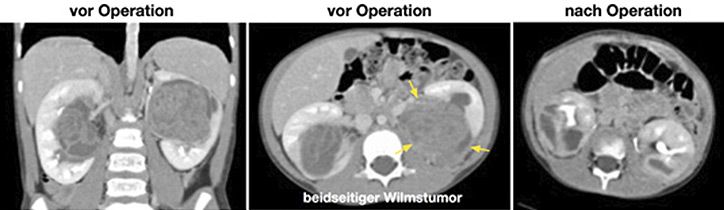

Die Behandlung von Kindern mit Nierentumoren findet standardisiert statt, maßgeblich ist hierbei das Studienprotokoll der SIOP Renal Tumor Study Group. In der Regel erhalten Kinder mit Wilms Tumoren initial eine Chemotherapie. Das Ansprechen auf die Therapie und die Bildgebung nach Chemotherapie enthalten hierbei wichtige Informationen für die Risiko-Einteilung der Tumoren. An die Chemotherapie schließt sich dann die Operation an. Kinder mit einseitigen Tumoren erhalten am häufigsten eine Entfernung der betroffenen Niere, wobei unter bestimmten Voraussetzungen ein Teil der Niere erhalten werden kann. Kinder mit beidseitigem Nierentumor sollten sofern möglich in jedem Fall Nieren-erhaltend operiert werden. Durch unsere Gruppe wurde für Kinder mit beidseitigem kompliziertem Befall der Nieren ein spezielles Operationsverfahren entwickelt (die sog. longitudinale partielle Nephrektomie), durch das oftmals ein Nieren-erhaltendes Vorgehen möglich ist, obwohl die Bildgebung dem zu widersprechen scheint. Wir operieren bei Kindern mit beidseitigem Nierentumor in der Regel beide Seiten in einem Eingriff. Auch die weiteren bekannten verkomplizierenden Faktoren werden durch uns operiert. Hierzu gehören Lungenmetastasen, die entfernt werden müssen, oder ein Befall der unteren Hohlvene, bei dem in Einzelfällen auch der Einsatz der Herz-Lungen-Maschine notwendig sein kann. Dies wird dann in Kooperation mit den Kollegen der Abteilung für Thorax-, Herz- und Gefäßchirurgie realisiert.